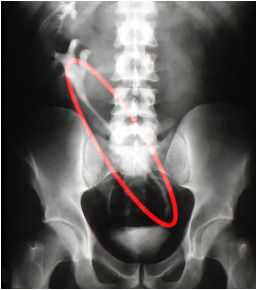

Ureter ectópico

Pielografía que muestra la anomalía desembocadura del ureter derecho. En circulo rojo, señala el trayecto oblicuo del ureter que cruza al lado opuesto y desemboca en la región posterolateral izquierda de la vejiga .